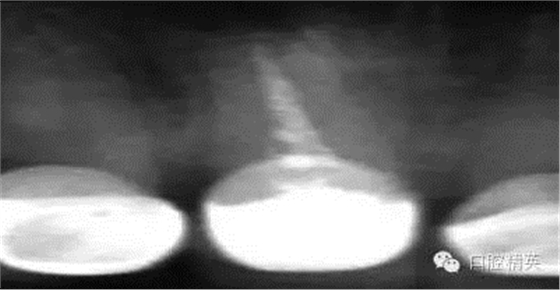

關(guān)于基礎(chǔ)治療。牙周治療和根管治療是美觀修復(fù)的基礎(chǔ)。根據(jù)術(shù)前檢查,常規(guī)先行全口潔治,必要時(shí)局部深層次的牙周治療,待牙周情況穩(wěn)定后,再考慮牙體預(yù)備與取模(見圖1、2)。在牙周炎未控制或牙齦紅腫的情況下,是不可能預(yù)備好牙齒,不可能取得清晰的印模,更談不上成功的美觀修復(fù)。